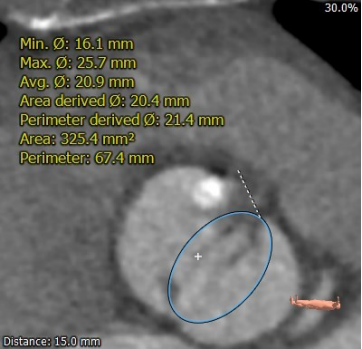

术前陈晓敏教授带领团队对这位患者进行了详细的分析,从CT分析结果显示,患者主动脉瓣为type 0型二叶瓣,瓣环直径为24.4mm,结合患者瓣叶钙化等情况,符合美敦力Evolut PRO 29mm瓣膜选型。经讨论决定以右侧股动脉为主入路,左侧股动脉为辅入路,术中进行23mm球囊预扩张,保证系统顺利跨瓣及释放,并采用世界先进的Cusp Overlap技术植入瓣膜 ,以更精准地释放瓣膜深,减少对患者传导系统的影响。